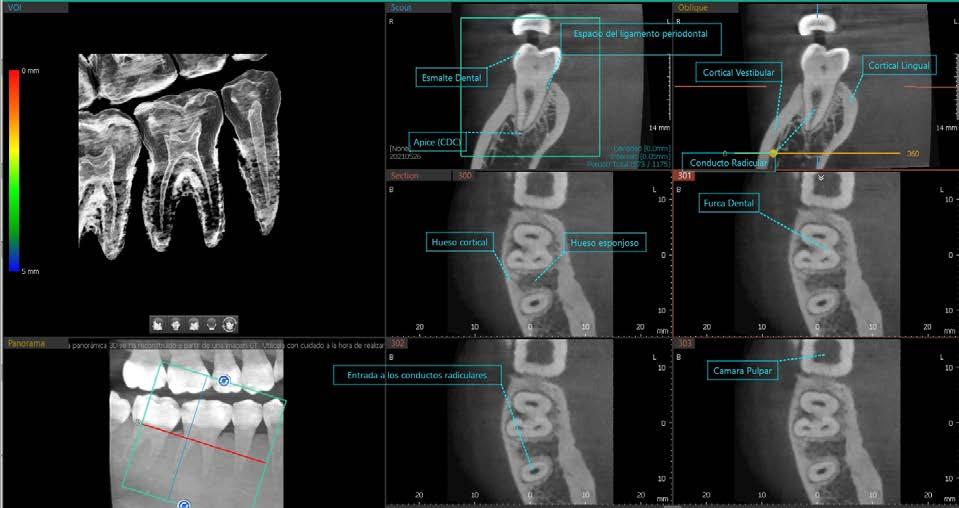

La Tomografía (CBCT) es una herramienta que proporciona imágenes 3D con menos dosis de radiación, además permite resultados más rápidos y exactos.

Con el MÓDULO ENDO del software Ez 3D-i podrás obtener imágenes de alta definición para una mejor exploración endoperiodontal.

MÓDULO ENDO de vatech

¿Sabías que entre más pequeño es el Voxel, mejor definición tendrán tus imágenes?

En vatech estamos comprometidos en brindar la mejor calidad en tecnología, por ello nuestros equipos cuentan con un voxel minimo de 0.0495 micras, en el FOV de 4x4, lo que permite un diagnóstico más preciso y optimo.